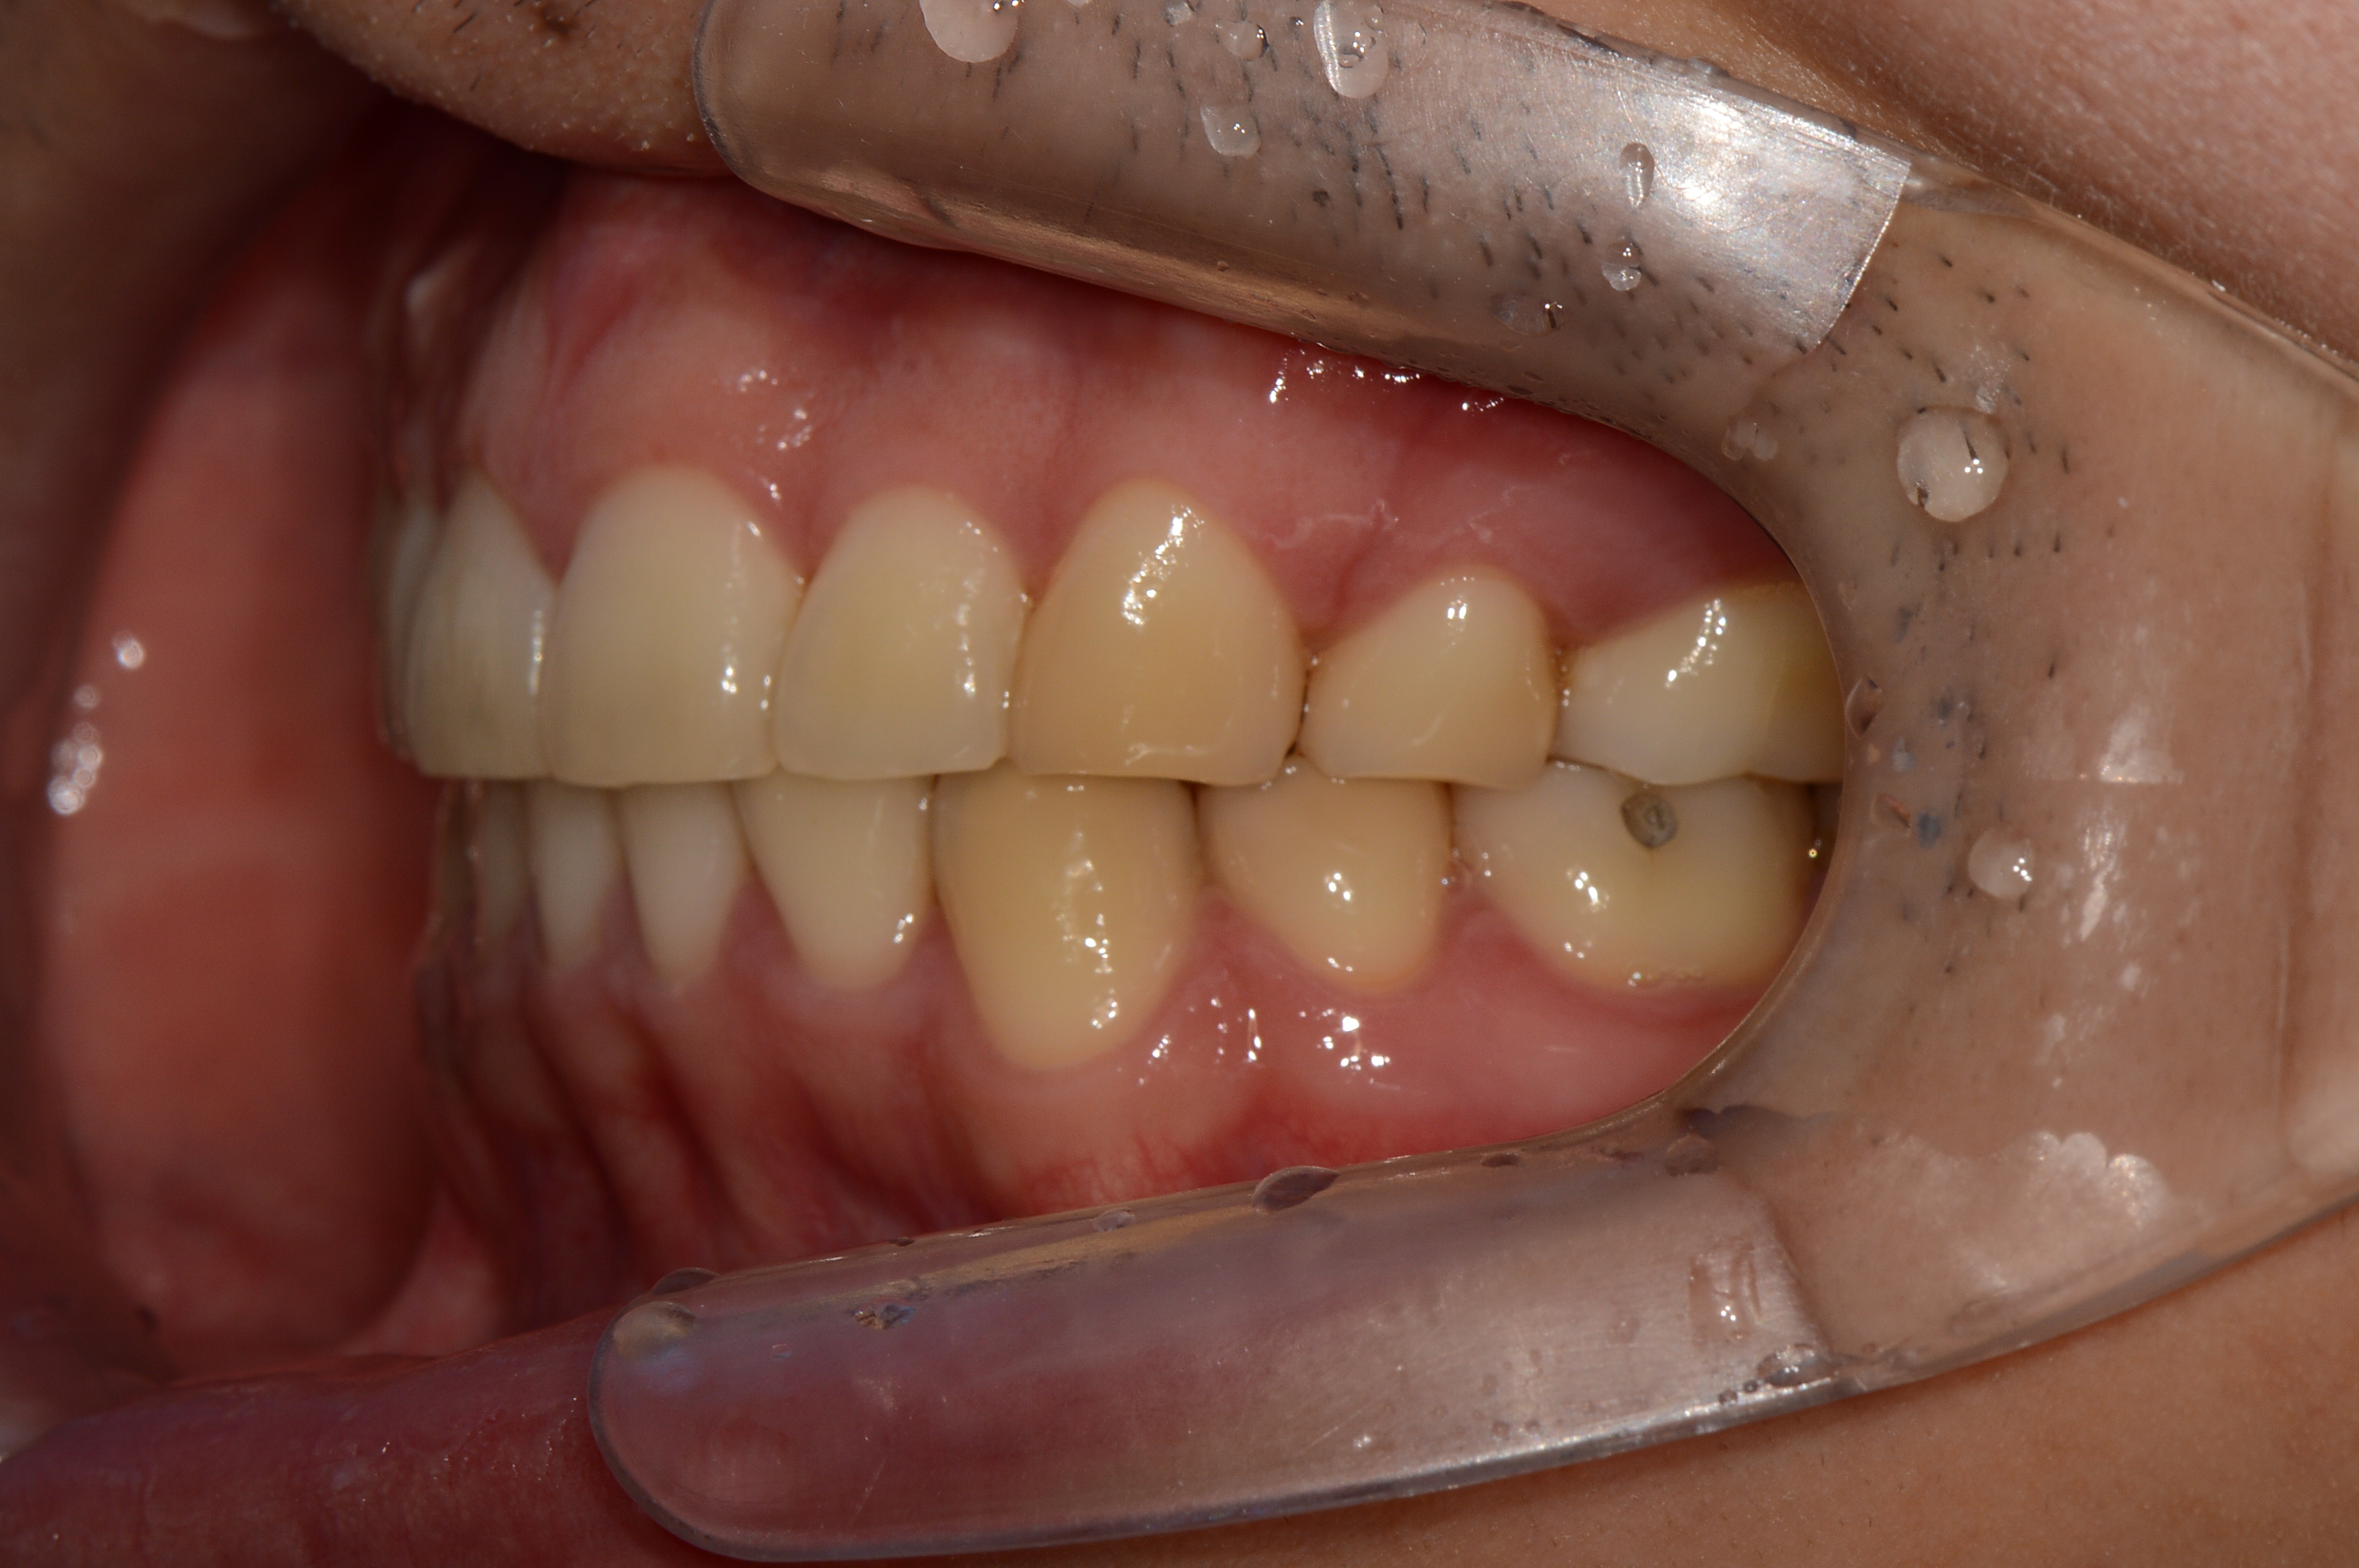

치료 후 사진입니다.